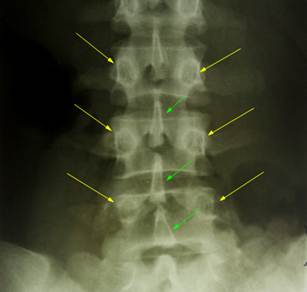

Слева

показан фрагмент прямой рентгенограммы позвоночника с нижними поясничными

позвонками, не имеющими ротации. Остистые отростки лежат на средней линии,

справа и слева от неё симметрично лежат тени ножек дуг позвонков. Справа

показан фрагмент прямой рентгенограммы позвоночника, на котором отображена

вершина сколиотической дуги в области 12 грудного и 1,2 поясничных позвонков.

Угол дуги большой (20°), выражены признаки ротации позвонков в области

вершины дуги: тени остистых отростков лежат не на середней линии тел позвонков,

тени правой и левой ножек дуг лежат не на одинаковом расстоянии от средней

линии тел позвонков. Зеленые стрелки – тени остистых отростков, желтые – тени

ножек дуг.